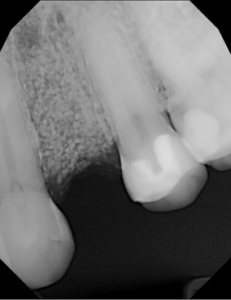

This video demonstrates alveolar ridge preservation following atraumatic surgical extraction of an endodontically treated tooth. Emphasis is placed on minimizing surgical trauma to preserve existing hard and soft tissues.

The case features flap management in the presence of a buccal dehiscence, followed by bone graft placement and stabilization using a dense polytetrafluoroethylene (d-PTFE) membrane. Surgical principles, membrane selection, and handling techniques are discussed to optimize ridge dimensions and facilitate future implant placement.